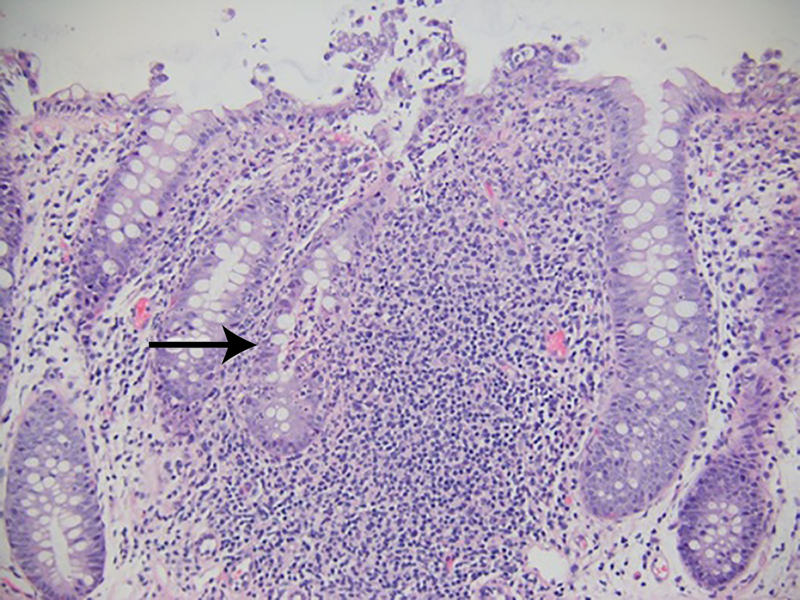

The patient underwent GI tract esophagogastroduodenoscopy 24 hours after admission. Results revealed severely inflamed, diffusely erythematous mucosa in the stomach (Figure 1A) and diffusely erythematous, congested mucosa with overlying exudate in the duodenum (Figure 1B). Gastric biopsy specimens demonstrated focally active gastritis without granuloma formation (Figure 2). Giemsa stain results were negative for Helicobacter pylori. Duodenal biopsy specimens showed active duodenitis with acute cryptitis, crypt abscess formation, and mild villous blunting without granulomas or viral inclusions (Figure 3). Results of colonoscopy with examination of the terminal ileum revealed mild colonic inflammation, extending from the rectum to the mid-ascending colon (Figure 4A). The most severe condition appeared to be in a rectosigmoid distribution. The proximal ascending colon and cecum appeared to be spared. The ileal mucosa appeared erythematous and edematous, with overlying exudate (Figure 4B). Biopsy specimens of the rectum, the sigmoid, and descending, transverse, and proximal ascending colon demonstrated mild active colitis with acute cryptitis, crypt abscesses, and neutrophils within the lamina propria (Figure 5). Biopsy specimens of the distal ileum showed moderate active ileitis with acute cryptitis, crypt abscesses, and focal architectural distortion (Figure 6).

Biopsy specimens of the rectum, sigmoid, and descending, transverse, and proximal ascending colon taken 2 weeks after ipilimumab administration showed active colitis with acute cryptitis, crypt abscesses, and neutrophils within the lamina propria (hematoxylin-eosin, original magnification ×100).